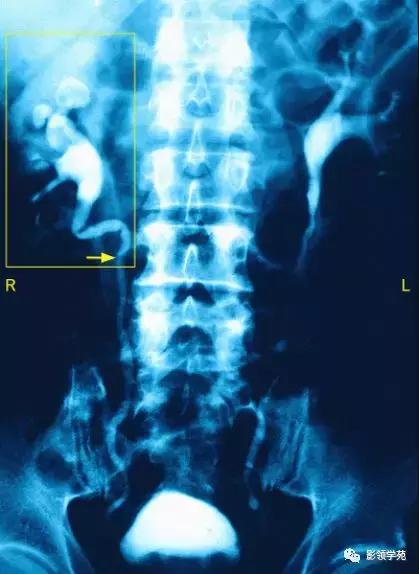

X线腹部平片检查可发现肠腔充气,并有液气平面、闭襻肠管影。上消化道泛影葡胺造影和小肠镜检查可观察近端小肠梗阻,但在怀疑有结肠梗阻的病人禁用消化道造影。腹部术后出现早期肠梗阻者,应注意是否存在低钾血症、术后早期炎性肠梗阻、术后胃肠无力症、术后肠麻痹、术后肠系膜血管栓塞或血栓形成等。